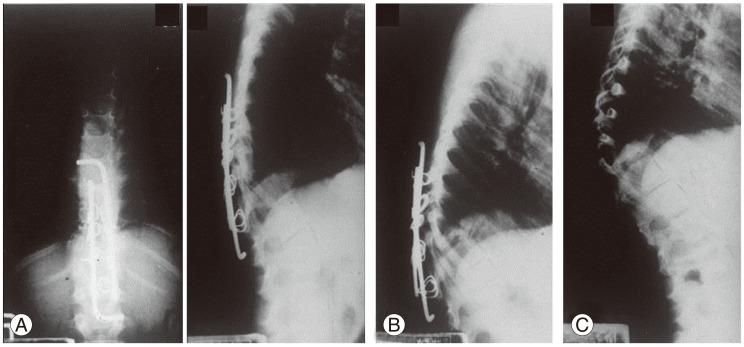

There were intra- and postoperative complications: direct large vessel and neurological injuries (cord, roots, nerves), late thrombophlebitis, various thoracic cavity problems, esophagus and ureter injuries, peritoneum perforation, ileus, wound infections, stabilization failure, increase of deformity and late adjacent joint and bone problems. Thrombophlebitis and sympatheticolysis symptoms and signs in the lower limbs were the most common complications related with anterior lumbar and lumbosacral surgeries. Kyphosis increased in 31.5% of the non-instrumented anterior surgery cases (42% in children and 21% in adults).

术中和术后出现了多种并发症:直接的大血管和神经损伤(脊髓、神经根、神经)、晚期血栓性静脉炎、各种胸腔问题、食管和输尿管损伤、腹膜穿孔、肠梗阻、伤口感染、内固定失败、畸形加重以及晚期相邻关节和骨骼问题。下肢血栓性静脉炎和交感神经松解症状及体征是与前路腰椎及腰骶部手术相关的最常见并发症。在未行内固定的前路手术病例中,31.5%出现驼背加重(儿童为42%,成人为21%)。